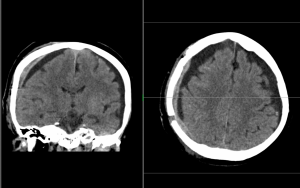

Ukázky snímků